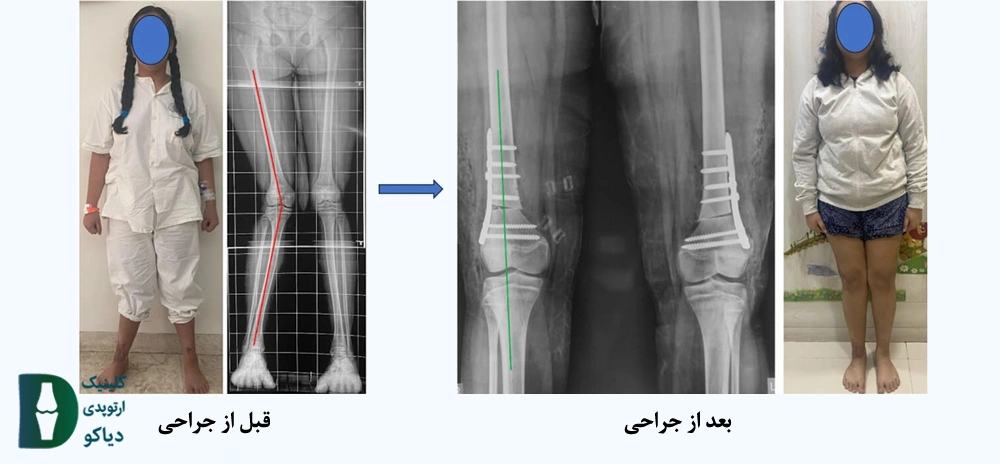

در شکل زیر تصویری از قبل و بعد از جراحی هدایت رشد نمایش داده شده است:

در تصویر زیر قبل و بعد از جراحی استئوتومی در یک نوجوان به نمایش در آمده است: